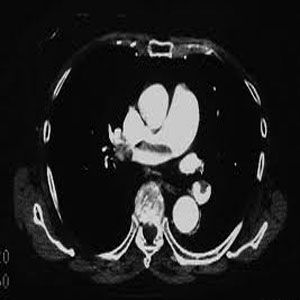

(1)肺部疾病:如肺炎、肺水腫、心跳呼吸驟停等,均能引起急性呼吸性酸中毒。肺氣腫肺部纖維性變、支氣管擴張、慢性支氣管炎等,由於肺組織彈性減低,不僅使肺泡通氣量減少,而且使肺內氣體不能很好的混合,常發生慢性呼吸性酸中毒。

(2)充血性心力衰竭或肺源性心臟病:因循環變慢CO2排出減慢,蓄積體內;又兼肺水腫或肺部病變,均可引起呼吸性酸中毒。

4.肺部疾病急性者可由急性呼吸窘迫綜合徵、急性心源性肺水腫、嚴重支氣管哮喘或肺炎、氣胸、血胸等引起。慢性者最常見的為慢性阻塞性肺病或肺組織廣泛纖維化等。